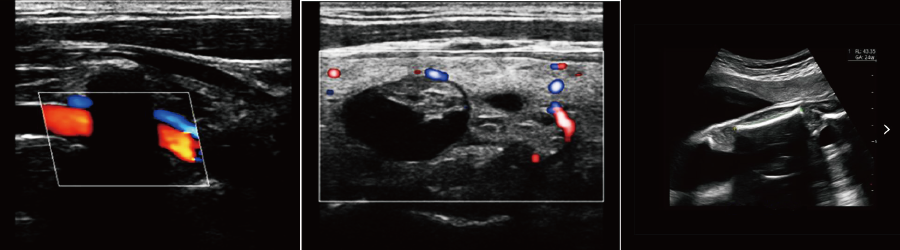

便攜式彩超機

●全家族探頭應用、微米成像技術、全激活兩個探頭接口

●IMT血管內中膜自動測量

●血流M(MC)成像

強大的功能和豐富的測量軟件,迅速而便捷地幫助您解決腹部、外周血管,婦科,產科,新生兒和小兒科,骨骼肌肉,心臟等各種臨床診斷的需要;